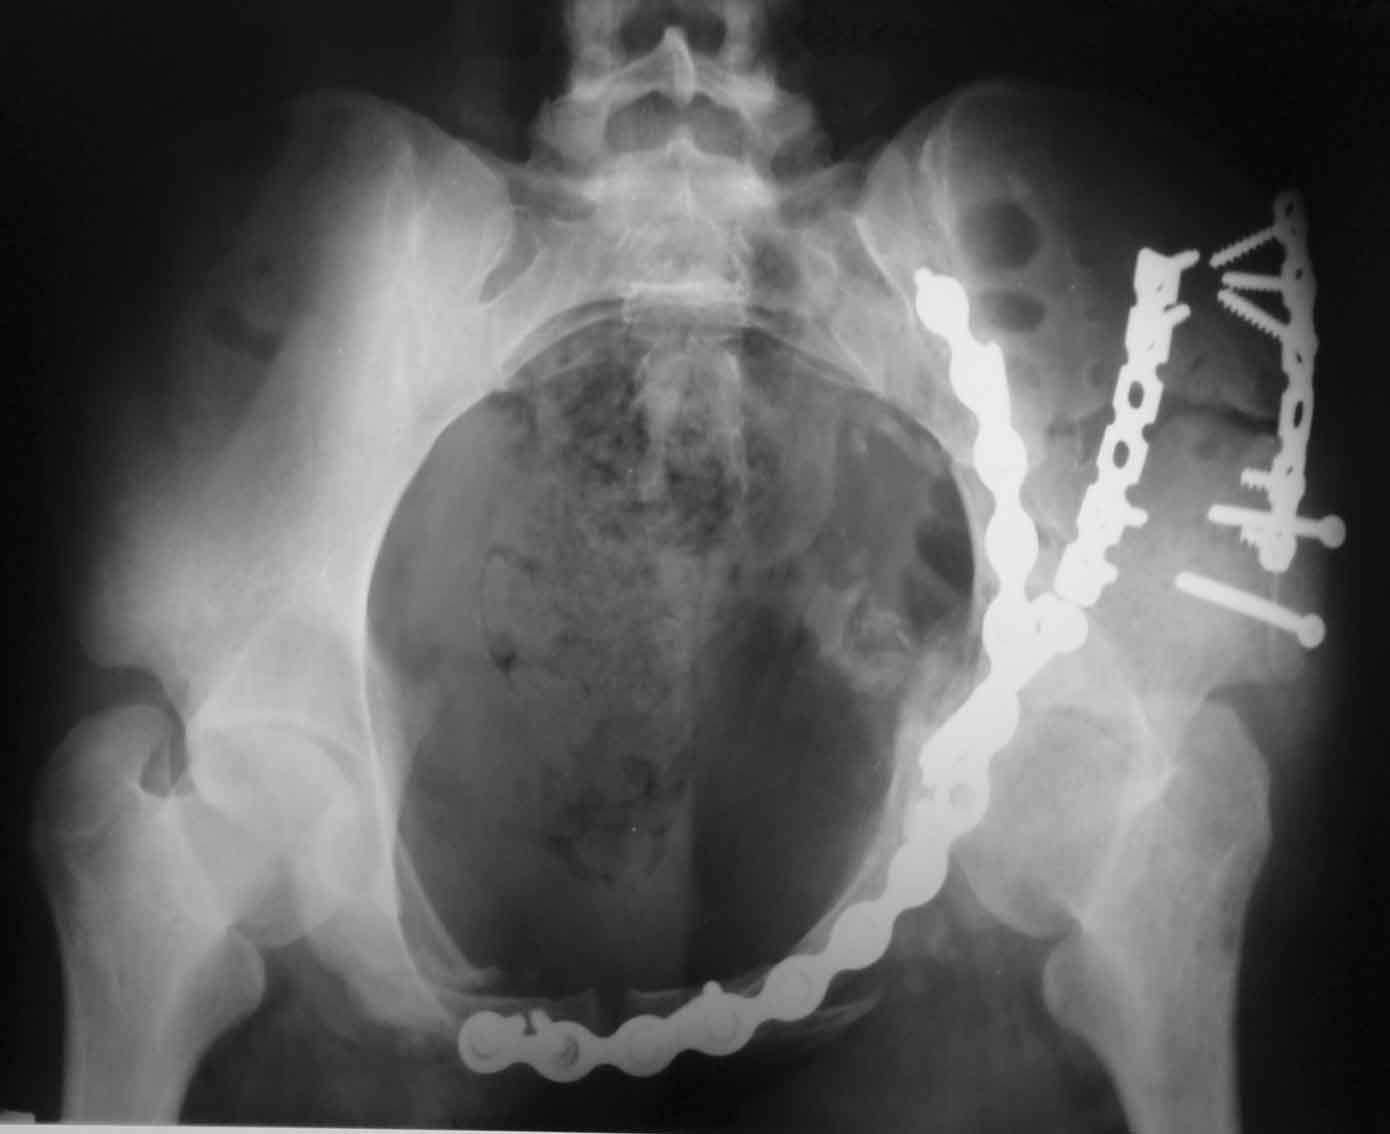

Рентгенограммы после операции

Прямая проекция